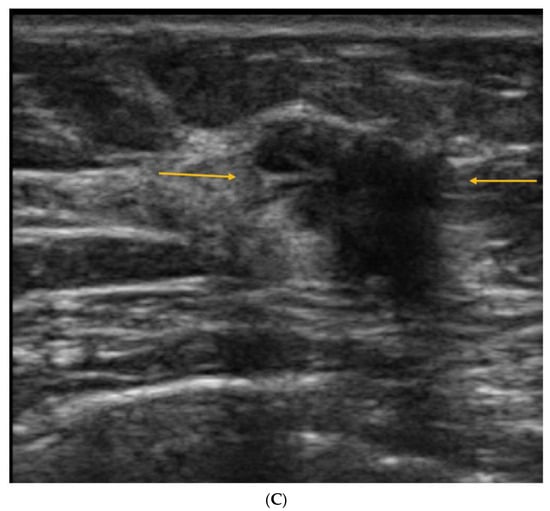

5. Ultrasound (US)